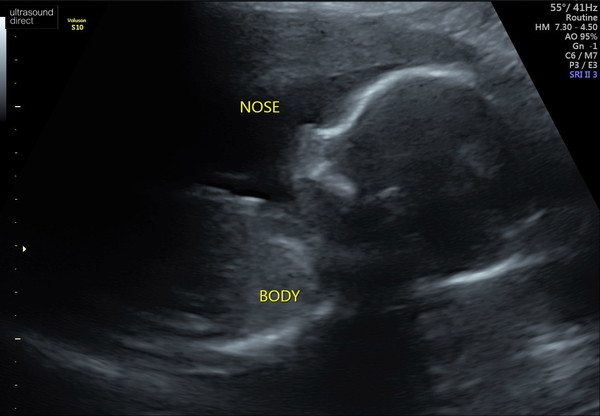

Hey guys had to go back to get another shot of the heart today but all was great and we managed to get some great photos too :)

She yawned and it was so clear ! So amazing! :)

March Babies #4

@whiskersonkittenss and @barnyb lovely scan pics! And that's great to see her yawn! @whiskersonkittenss are you feeling better today hun? @ELW85 I'm sure we will :) going into 20 weeks next week I'm sure we will feel more

@barnyb what beautiful scan pics!! In 2 of my scans my baby looks like she's picking her nose.. not quite as cute as a yawn!😂

@whiskersonkittenss lol that's lovely photos! Also it's funny that you think baby looks like you! Because I think baby looks more and more like her dads side profile 😂 luckily he has a lovely side profile 😁